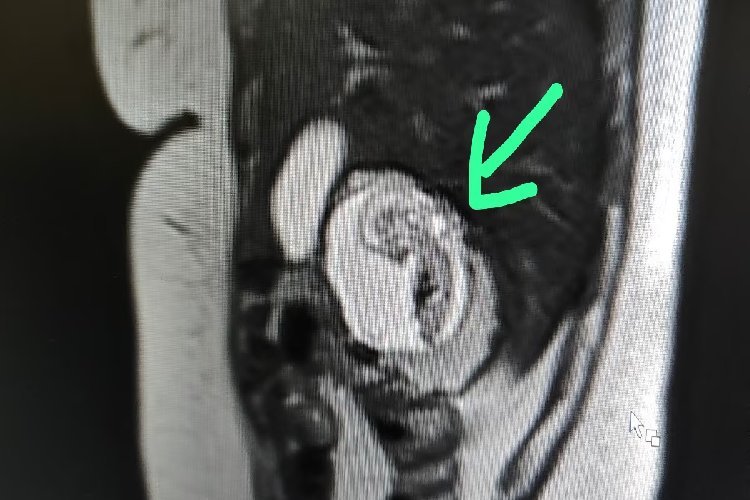

बुलंदशहर: उत्तर प्रदेश के बुलंदशहर जिले में एक दुर्लभ गर्भावस्था का मामला सामने आया है, जिसने डॉक्टरों को हैरान कर दिया है. 30 वर्षीय स्थानीय निवासी एक महिला को लगातार पेट दर्द की शिकायत थी, जिसके बाद उन्होंने चिकित्सकीय सहायता लेने का फैसला किया. उनके पेट का एमआरआई स्कैन कराया गया, जिसमें एक चौंकाने वाला खुलासा हुआ. एमआरआई में पता चला कि 12 सप्ताह का गर्भ उनके गर्भाशय में नहीं, बल्कि उनके लिवर में था.

भ्रूण को उनके लिवर के दाहिने हिस्से में पाया गया, जिसकी पुष्टि रेडियोलॉजिस्ट डॉ. केके गुप्ता ने की, जिन्होंने उनकी जांच की थी. स्कैन के दौरान उन्होंने भ्रूण की दिल की धड़कन भी देखी. यह महिला बुलंदशहर की निवासी है, एक गृहिणी है और दो बच्चों की मां है. उनके पति एक निजी कंपनी में नौकरी करते हैं. लगभग दो महीने से, उन्हें अस्पष्ट पेट दर्द और उल्टी की शिकायत थी. कई डॉक्टरों से परामर्श और विभिन्न जगहों पर इलाज के बावजूद उन्हें कोई राहत नहीं मिली.

एक निजी इमेजिंग सेंटर में एमआरआई स्कैन के लिए रेफर किए जाने के बाद ही उनके दर्द का असली कारण सामने आया. चिकित्सा सूत्रों के अनुसार, भारत में पहले कभी ऐसा कोई मामला सामने नहीं आया है. एमआरआई करने वाले डॉ. गुप्ता ने कहा, "यह 12 सप्ताह की पुष्ट गर्भावस्था थी, जो गर्भाशय के बजाय लिवर में थी." उन्होंने आगे बताया कि स्कैन के बाद उन्होंने इस स्थिति पर व्यापक शोध किया और पाया कि यह एक अत्यंत दुर्लभ घटना है, जिसमें विश्व भर में अब तक केवल 18 ऐसे मामले दर्ज किए गए हैं.